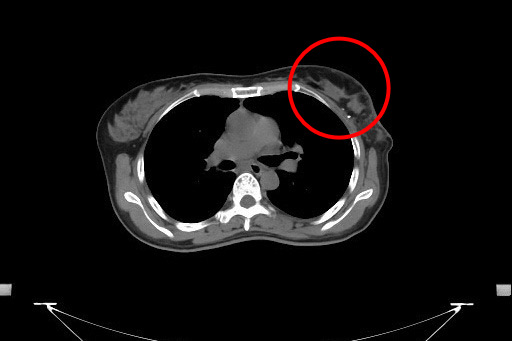

乳房醫學中心張群明主任表示,若是腫瘤較大、多發性腫瘤、腫瘤位於乳房中央或侵犯乳頭、乳房攝影顯示廣泛性或多發性癌樣鈣化點(原位癌)、發炎性乳癌、手術後不做放射線治療,以上任一種情況都建議做乳房全切除手術;但若腫瘤較小,切除後乳房仍能保有良好外觀且能接受手術後放射治療的病友,則適合乳房部分切除手術(保留手術)。

早期乳癌患者有些人的腫瘤較小,不需將整個乳房切除,除了可以做部分乳房切除手術,並可同時進行整型式乳房重建手術。切除腫瘤保留部分健康的乳房組織,並將組織轉位來填補切除腫瘤後所留下來的乳房空洞,重建乳房的缺損,手術後乳房的外觀不會產生明顯的凹陷,能保留較佳的外觀,整型式乳癌切除手術也是目前乳房手術的趨勢。

隨著微創手術器械的進展,有些患者可以進行內視鏡輔助整型式乳癌切除手術,從位於胸部側邊靠近腋下約五公分大小的單一傷口,進行腋下淋巴結取樣或清除,並由此進行乳房部分切除手術,將所要切除的乳房組織取出後再進行乳房整型修補。張群明主任分享,經醫師評估腫瘤的大小與位置,合適者可以進行「內視鏡輔助整型式乳癌切除手術」,以自己的乳房做整型修補,術後乳房不會產生凹陷且不會在乳房上留下任何傷口。